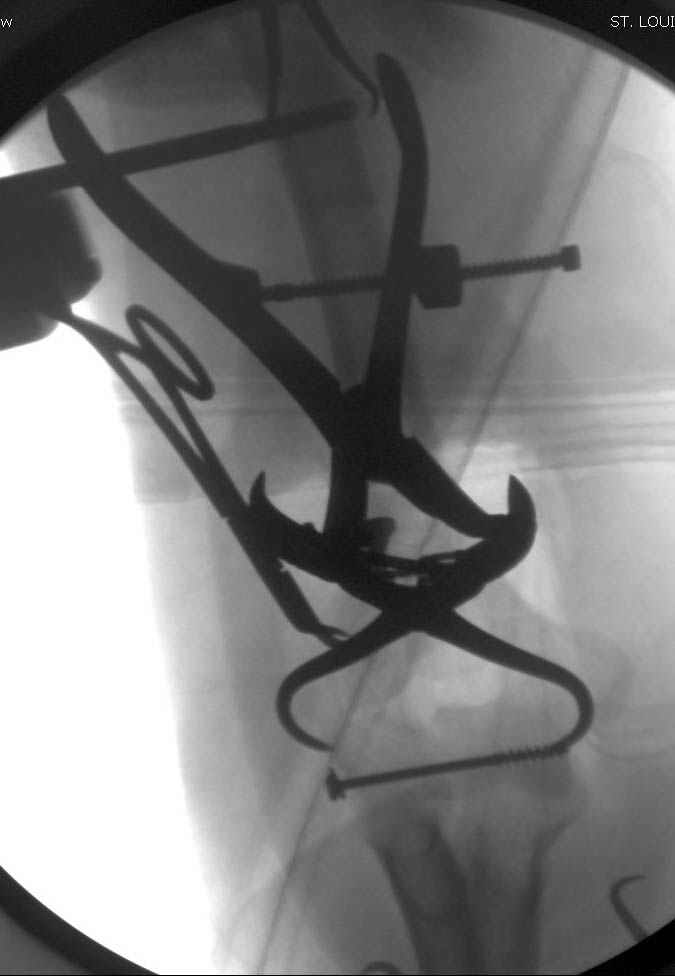

Примерный случай, только перелом был открытый, в задне-медиальной стороне рана около 2 см по характеру "изнутри кнаружи", неврологический статус со слабостью сгибания мизинца, также слабая абдукция и аддукция указательного пальца и сгибания в кисти.

Больному сделали обработку и наложили временный аппарат внешной фиксации плечо-предплечье.

На шестой день сделали открытую репозицию чрезлоктевым доступом двумя locking plate, локтевой нерв был ушибленным, после операции положительная динамика в Flexor Carpi Ulnaris. Фиксацию локтевого отростка произвели tension band technique с дополнительным шурупом.

Этапы операции на снимках....